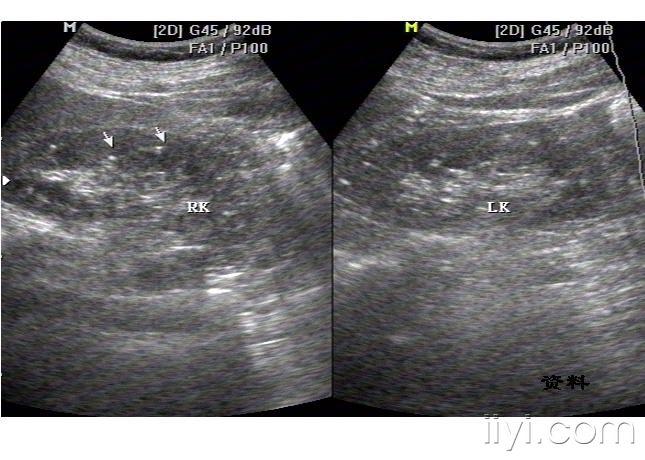

双肾钙乳沉积

图片尺寸480x329